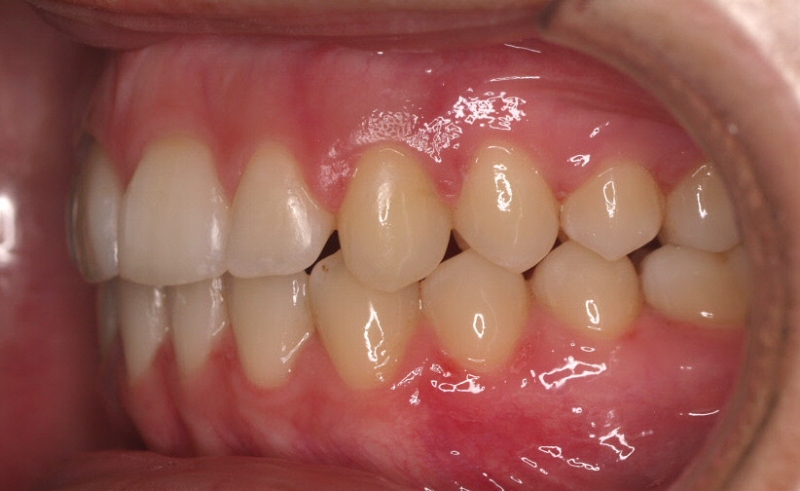

Clase II paciente 15 años

La paciente O.O. acude a nuestra consulta por:

– Canino 13 e incisivo lateral 42 en posición ectópica.

– Canino 23 incluido.

Con lo que decide realizarse un tratamiento de ortodoncia de duración de 24 meses con brackets damon Q.